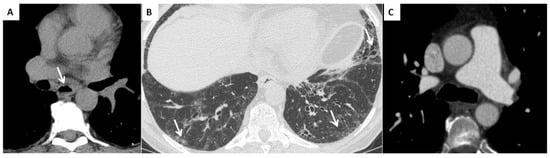

Interstitial lung disease (WHO Group III of pulmonary hypertension). ILD is present in up to 90% of patients with SSc [43]. The most common ILD in the SSc patient is the NSIP pattern, characterized by a different degree of inflammation and fibrosis (cellular and fibrotic NSIP). The cellular NSIP pattern is characterized by the presence of ground glass opacities with a bilateral and symmetrical distribution; when fibrotic changes occur (fibrotic NSIP pattern), irregular septal thickening, bronchiectasis and bronchiolectasis can be recognized on HRCT as superimposed features on a background of pre-existing ground glass opacities [43]. The usual interstitial pneumonia (UIP) pattern is less common in SSc and this pattern is characterized by the presence of irregular septal thickening in the peripheral and subpleural regions of the lungs, honeycombing, traction bronchiectasis and pulmonary volume loss. This pattern has a worst prognosis and a faster progression [3] (Figure 3).

Combined pulmonary fibrosis and emphysema syndrome (WHO Group III of pulmonary hypertension). This is a relatively new entity characterized by the presence of emphysema, both paraseptal and centrilobular, in upper lobes in association with lung fibrosis in lung bases. It occurs most often in smokers. This syndrome is associated with a higher risk of developing pulmonary hypertension and is described in patients with connective tissue diseases, including SSc patients [44]. Moreover, it can be identified in SSc patients with no history of smoking exposure [45].

Pulmonary veno-occlusive disease (WHO Group I of pulmonary hypertension). This rare condition is characterized by a diffuse obstruction of the small pulmonary veins. Typical HRCT findings are represented by the presence of centrilobular ground glass opacities, septal thickening, and lymph nodes enlargement. POVD-like aspects are common in patients with SSc-PH [46].

SSc patients with pulmonary hypertension and radiological signs of POVD have a worst prognosis compared with those patients without them therefore it is important to distinguish this phenotype not only at the baseline CT examination but also during follow-up [47].

Chronic thromboembolic pulmonary hypertension (WHO Group IV of pulmonary hypertension). SSc patients are at higher risk of developing chronic thromboembolic disease, and this form of PH that can be surgically treated. Typical vascular signs of CTEPH can be detected on CT angiography, including vascular stenosis, retraction with total or subtotal obstruction, recanalization or residual bands within the vascular lumen. Dilatation of systemic supply is another feature, which is the abnormal enlargement of bronchial, intercostal, phrenic and internal mammary arteries [48].

Cardiac features of PH are represented by a right ventricle hypertrophy, defined as a wall thickening of more than 4 mm or leftward bowing of the interventricular septum, and right ventricular dilatation, defined as a right ventricle to left ventricle diameter ratio of more than 1:1 at the midventricular level on axial image. [49].

Moreover, linear bands, due to previous pulmonary infarction, mosaic pattern of perfusion, bronchial wall thickening and cylindrical airway dilatation (segmental and subsegmental bronchi) are typical parenchymal features of chronic pulmonary hypertension detectable on CT scan [37,50].

Figure 3. (A) Esophageal involvement in a 56-year-old male with a diagnosis of SSc. Axial image with a mediastinal window setting shows a dilatation of the esophagus (diameter >1.2 cm) with an air-fluid level (white arrows); (B) Parenchymal signs: axial high resolution CT scan shows a fibrotic NSIP pattern due to the presence of diffuse irregular septal thickening, bronchiectasis and bronchiolectasis on a background of diffuse ground glass opacities (white arrows); (C) Vascular signs: a main pulmonary artery with a diameter greater than 36 mm measured in a scanning plane of its bifurcation is a sign of pulmonary hypertension.